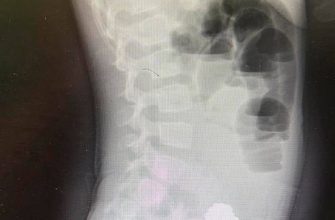

Девочку экстренно госпитализировали с кишечной непроходимостью